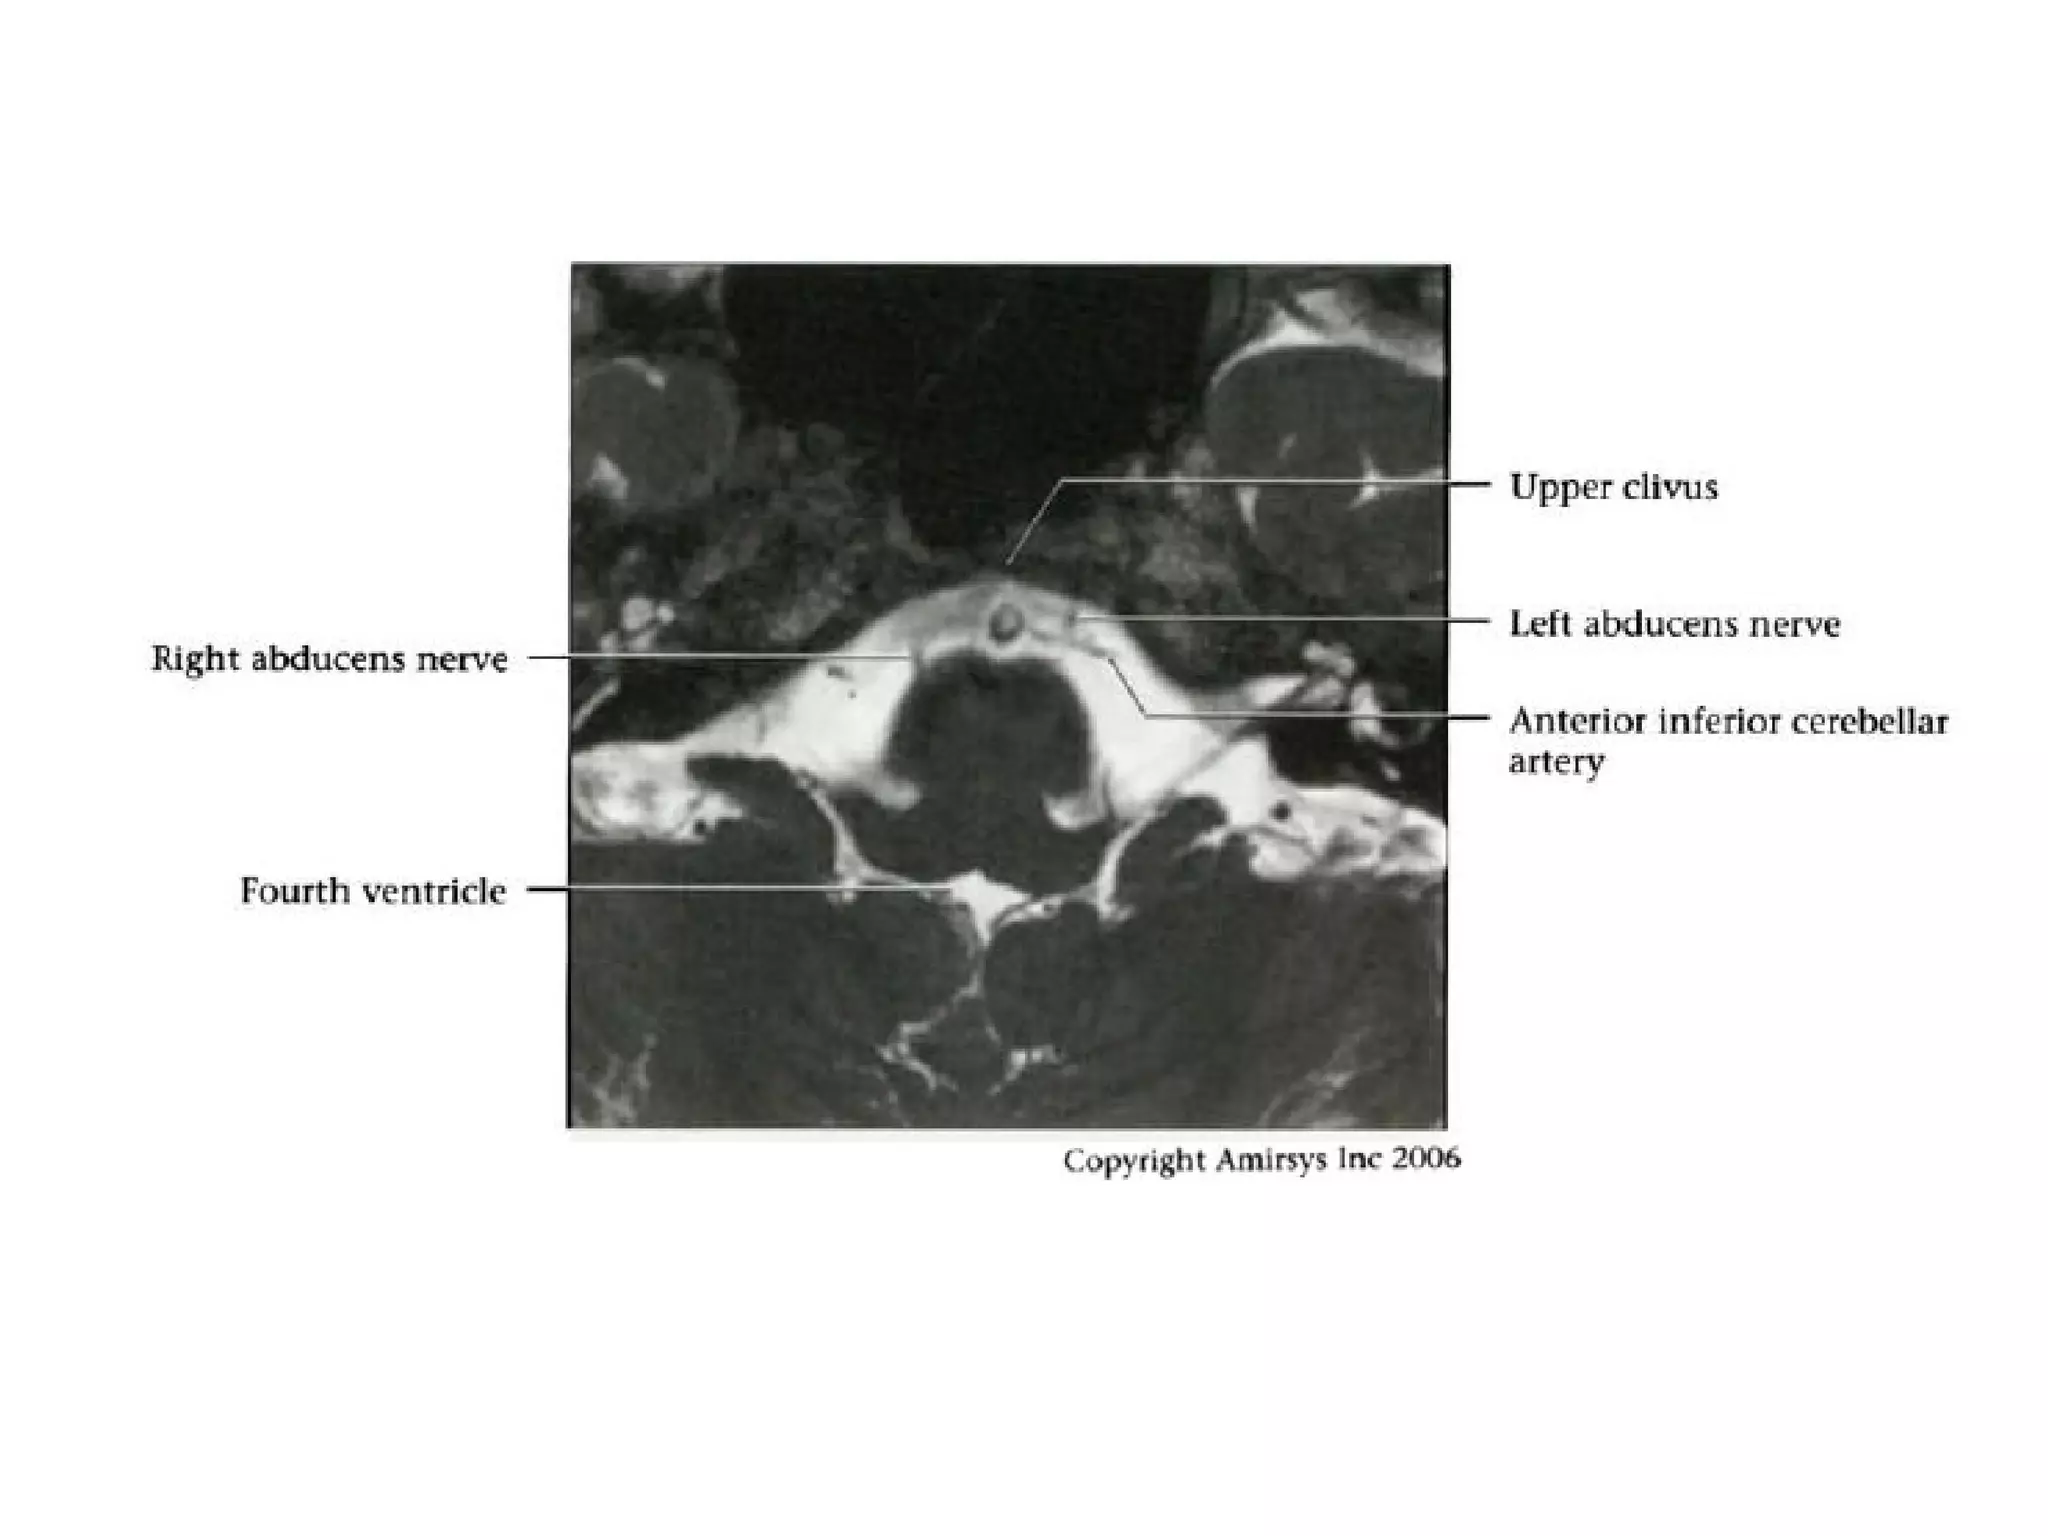

Cranial Nerve VI:

The Abducens Nerve

• The abducens nerve emerges from nuclei anterior to the

fourth ventricle, then courses anteriorly through the pons

to the pontomedullary junction and into the prepontine

cistern.

• After crossing the prepontine cistern in a posterior-to-

anterior direction, the abducens nerve runs vertically

along the posterior aspect of the clivus, within a fibrous

sheath called the Dorello canal.

• The nerve then continues over the medial petrous apex

and through the medial cavernous sinus, entering the

orbit through the superior orbital fissure to innervate the

lateral rectus muscle.

RadioGraphics 2009; 29:1045–1055

• It is important to note that the abducens nerve

runs almost the entire length of the clivus.

• Radiologists should be vigilant for clivus and

petrous apex abnormalities in the setting of

abducens nerve palsy.

• Although the abducens nerve lies near the

anterior inferior cerebellar artery and has a

similar caliber, the two structures course in

orthogonal directions and are thus easily

distinguished.

Abducens nerve.

Axial 0.8-mm-thick SSFP MR image at the level of the

pontomedullary junction shows both abducens nerves (arrows)

where they traverse the prepontine cistern.

The bottom of the pons (p) and the top of the medulla (m) are

visible in this section, and the cerebellopontine angle (CPA) and

basilar artery (arrowhead) are important anatomic landmarks.

Axial 0.8-mm-thick SSFP MR image shows the abducens nerve

where it enters the Dorello canal (arrow) along the posterior

aspect of the clivus.

Vascular landmarks include the basilar artery (black arrowhead)

and the anterior inferior cerebellar artery (white arrowhead).